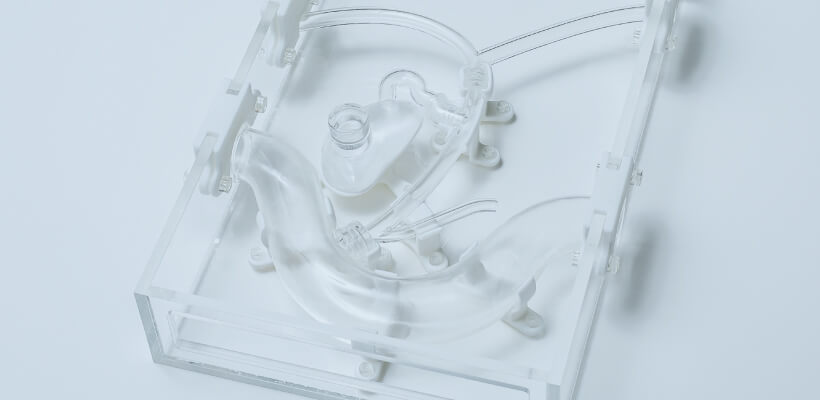

- Reads DICOM data obtained from CT imaging into mimics

- Eliminates noise (artifacts) generated by metal and other materials

-

We will convert the data into 3D data

and confirm with the customer that

the area of interest has been reproduced in the image or data.*If the STL output is available directly from the medical workstation,

the above process is eliminated. - 3D printing output